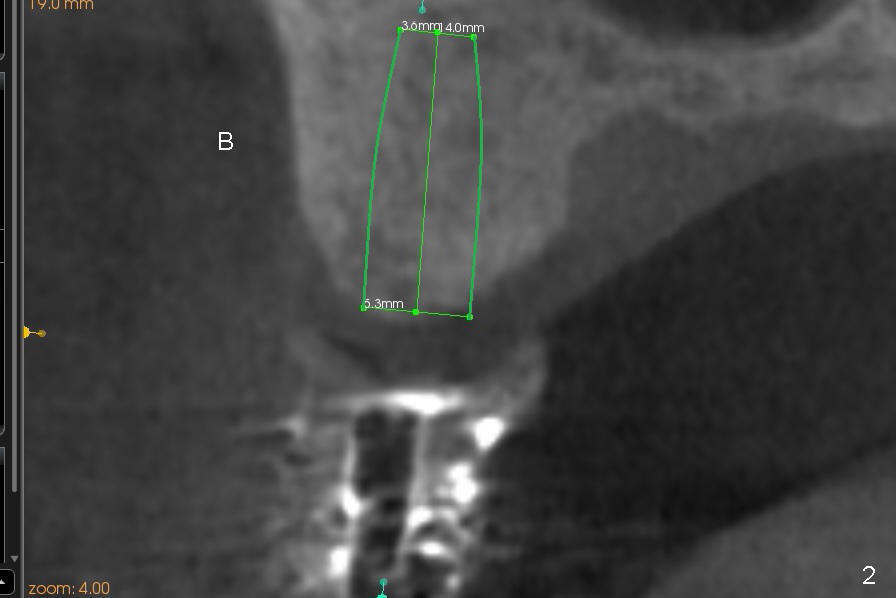

First molar occlusion is planned (1,2). The tooth #3 was extracted a year ago (Fig.1 (CT sagittal section). There is more bone loss distally so that bone graft (red circles) is required post implantation (5.3x14 mm). Buccolingual width is not severely compromised (Fig.2 (coronal section), 3).